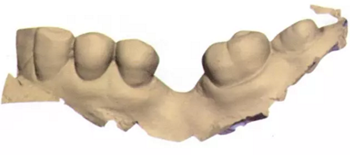

3b:無(wú)牙區(qū)的表面掃描

圖3c:表面掃描之后左側(cè)下頜骨區(qū)的重建圖

圖3d:在最大交錯(cuò)位數(shù)字化重建牙弓

在此次就診中,也用TRIOS掃描儀(3Shape;圖2與圖3b-d)掃描左側(cè)上下頜骨和上下牙弓并進(jìn)行咬合重建。只要把所有的診斷信息收集起來(lái),第二天就可以復(fù)診治療。